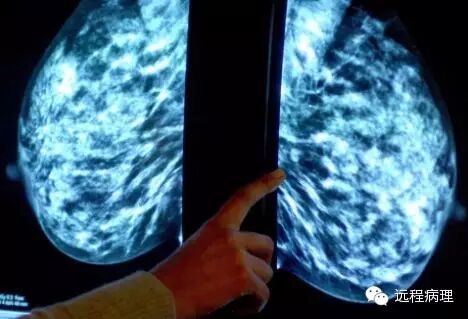

天文学家现与肿瘤学家合作,将曾用来区分单个恒星和遥远星系的电脑软件用于检测乳腺肿瘤的类别。

“原为寻找宇宙内超新星而设计的技术,现在正被用于癌症的诊断。”据英国《每日邮报》网站3月10日报道,天文学家现与剑桥大学的肿瘤学家组成工作小组,将曾用来区分单个恒星和遥远星系的电脑软件用于检测乳腺肿瘤的类别。发表在《英国癌症杂志》的一篇研究报告显示,研究人员曾使用天文软件来分析2000名乳腺癌患者的肿瘤情况。报告显示,该软件可作出与人类病理学家一样准确的判断,并在某些情况下,它得出的分析更加客观。

天文学研究所的研究员尼古拉斯·沃尔顿说:“天文学家经常用这种软件来处理从望远镜发回的大量数据,这其实跟病理学家的工作差不多,都是通过形状和颜色的观测来更好地了解他们的研究对象。”此前,癌症细胞的分析工作是由人类病理学家通过显微镜检测组织样本来完成的。而现在的新方法是,通过化学处理癌细胞来使细胞内某些蛋白质被染成棕色,再将用高分率扫描仪建立的细胞的数字化图像传送至软件中,软件会根据细胞内棕色区域的位置来判定癌症类型。